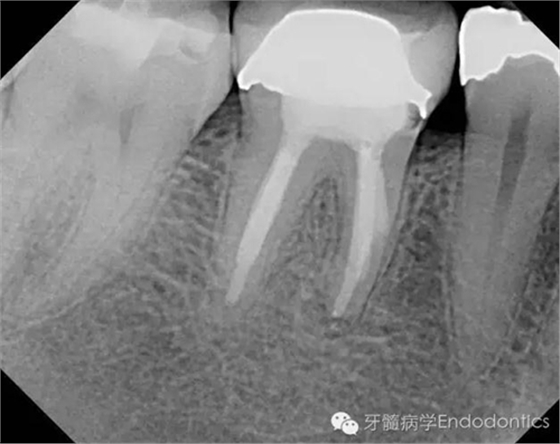

圖1.術(shù)前X線片(a)

圖2.術(shù)前X線片(b)